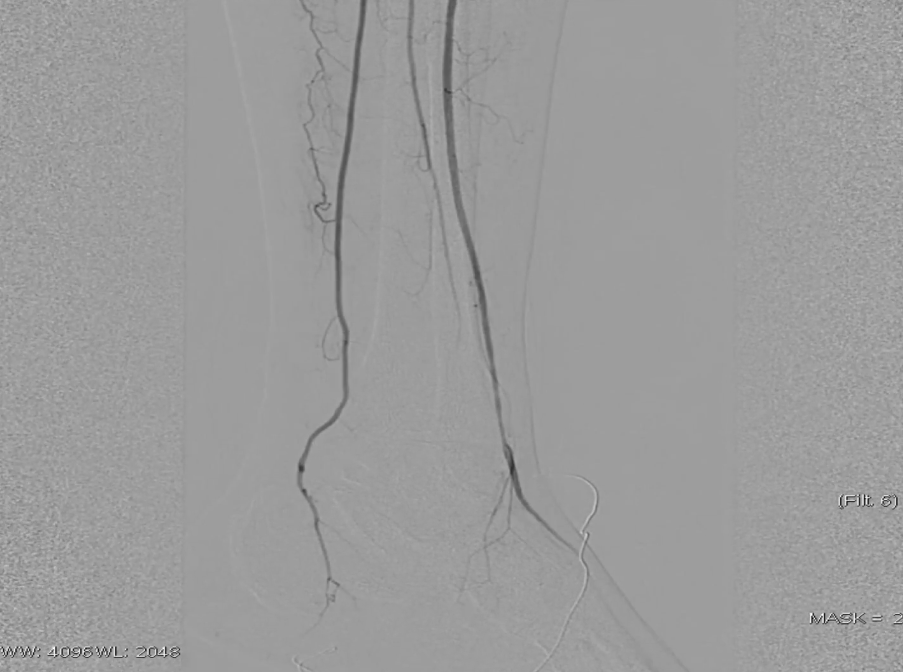

先用5mm长球囊充分预扩张;再次造影显示,股浅动脉近中段管腔获得良好,中远段仍有大量的夹层

采用药物涂层球囊(DCB)对股浅动脉病变段全程覆盖:近端用5-250新型药涂球囊,远端用5-150 impact 药涂球囊;

造影显示中段仍有局限性夹层,为保证远期通畅率,植入补救性支架并以5mm球囊后扩张